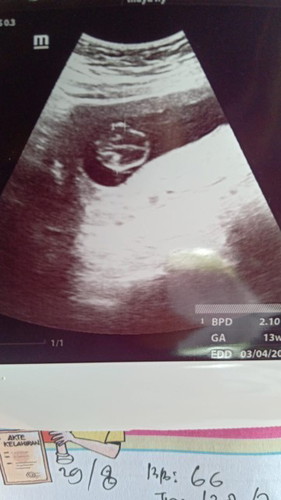

Usia kandungan 13 minggu

Alhamdulillah pertama kali usg trnyata usia kandungan 13 minggu, kmaren perkiraan bu bidan 11 minggu. Dan Alhamdulillah janin ku sehat , aktip kata dokter ya, detak jantung ya normal. Terimakasih Ya Allah semoga sehat lancar sampai melahirkan😍🤗🥰